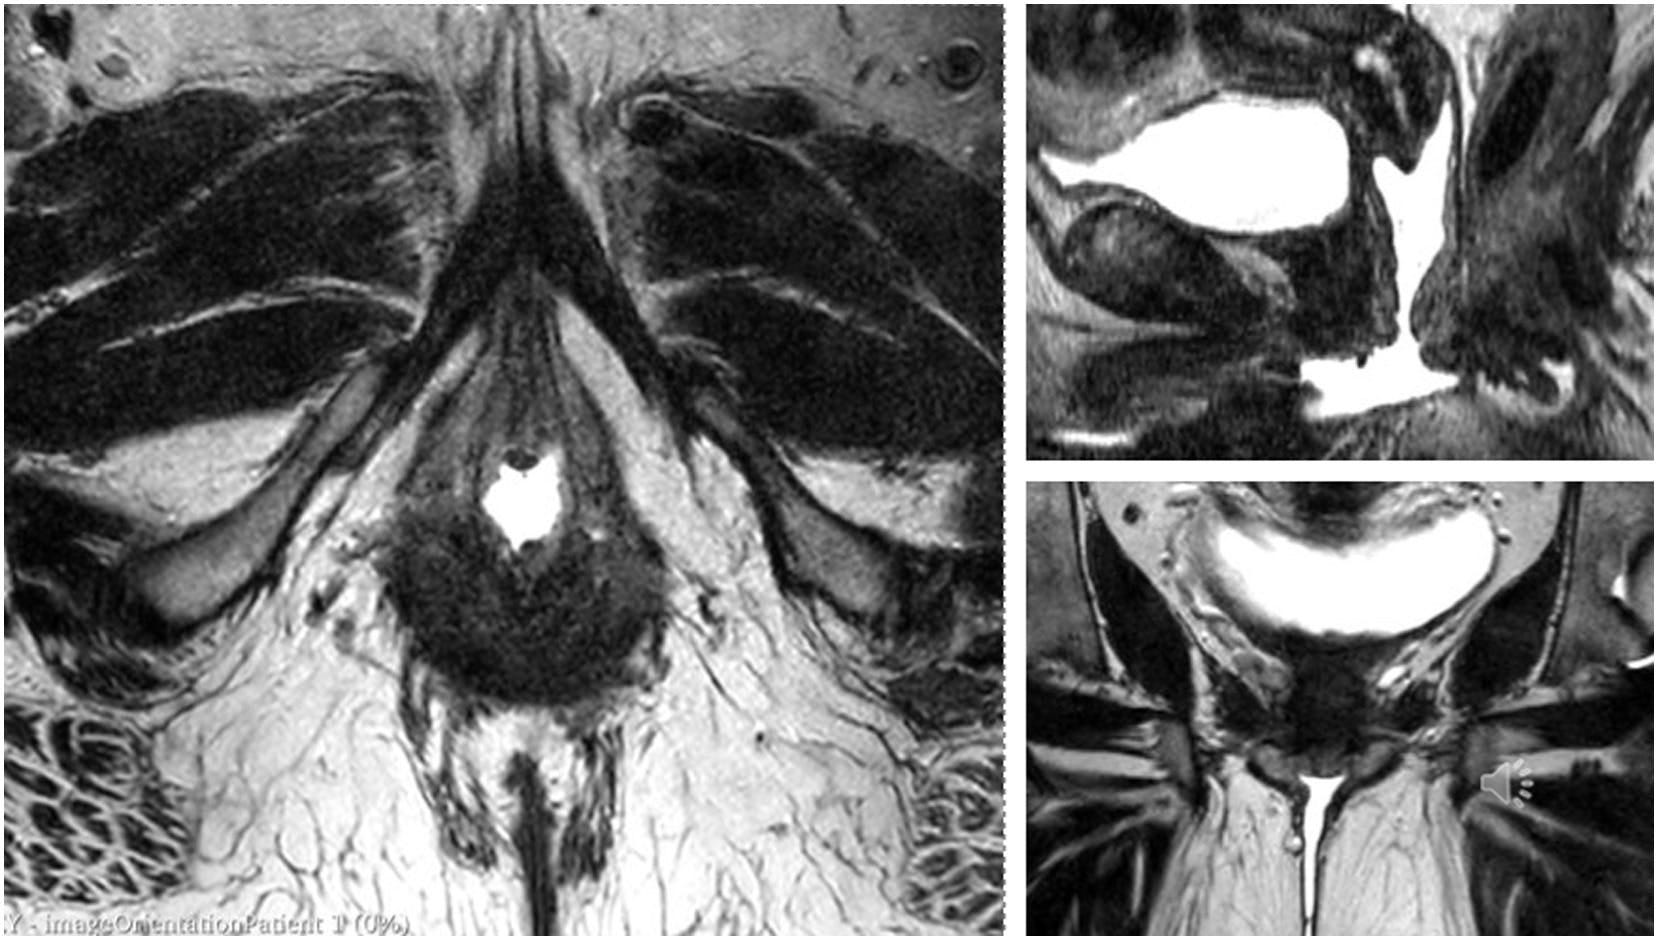

In the early 2000s, pioneering research by Dr. Helen O’Connell and colleagues used 3D magnetic resonance imaging to reveal the true size, shape, and depth of the clitoral complex. These scans confirmed that most so-called “vaginal” orgasms are actually mediated by clitoral tissue — even when the stimulation feels internal.

MRI-enhanced anatomical view of the clitoral complex in situ, illustrating how the glans, shaft, crura, and vestibular bulbs align with surrounding pelvic structures. (Source: recent 3D MRI data — American Journal of Obstetrics & Gynecology tutorial.)

-Female orgasm | Female anatomy and biology